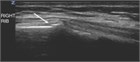

This chapter discusses diagnosis and management of uncomplicated rib fractures.

A patient with an isolated rib fracture or a minor costochondral separation usually has recently fallen, injuring the side of the chest; been struck by a blunt object; coughed violently; or leaned over a rigid edge. The initial chest pain may subside, but over the next few hours or days the pain increases with movement, interferes with sleep and activity, and becomes severe when the patient coughs or breathes deeply. The patient is often worried about having a broken rib and may have a sensation of bony crepitus or abnormal rib movement. Breath sounds bilaterally should be normal unless there is substantial splinting or a pneumothorax or hemothorax is present. There is point tenderness over the site of the injury, and occasionally bony crepitus can be felt.